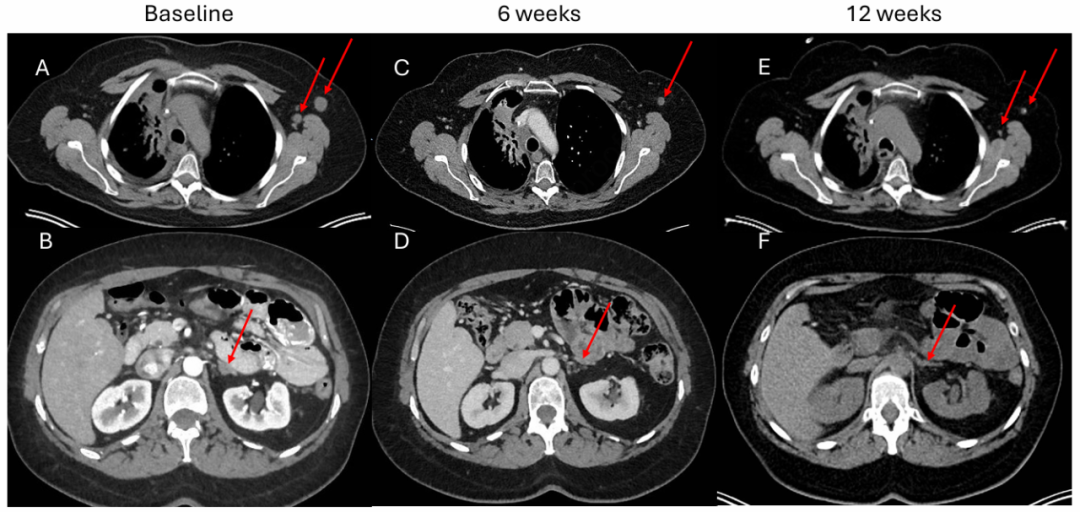

在患者初次确诊后11个月(图1),基于其癌症具有侵袭性临床特征和先前文献记录的肺类癌中DLL3表达,患者开始接受Tarlatamab治疗。治疗开始后进行了DLL3免疫组化检查,结果显示100%的细胞均强烈表达(图2)。

在Tarlatamab治疗第1周期第3天,针对脑转移瘤接受了立体定向放射外科(SRS)治疗。Tarlatamab治疗6周后CT显示产生治疗反应,左腋窝淋巴结从1.5 cm缩小到0.9 cm,左肾上腺结节从1.3 cm缩小到0.5 cm(图3,A-D)。先前放疗的右侧气管旁肿块从2.4 cm缩小到1.9 cm,隆突下淋巴结从1.6 cm缩小到1.1 cm。第12周的PET/Dotatate成像(图3E-F)显示右肺门肿块、左肾上腺结节和左腋窝淋巴结进一步减小。右侧气管旁的标准摄取值(SUV)从基线6.4降至4.7,左腋窝从2.2降至1.3,左额颅骨病变从2.4降至1.2。不幸的是,脑部MRI发现了两个非常小的新病变,采用SRS治疗第二疗程,并继续使用Tarlatamab。在前四个疗程的Tarlatamab治疗中,没有发生细胞因子释放综合征(CRS)或免疫效应细胞相关神经毒性综合征(ICANS)。第1疗程期间出现了1级疲劳,现已缓解,1级味觉障碍一直持续存在。

图3